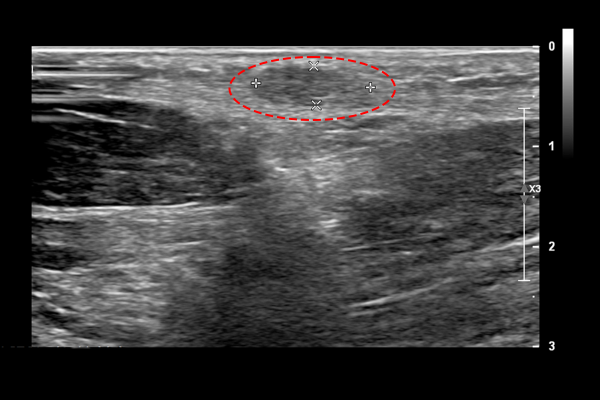

신체검진상 발바닥 아치부위를 눌렀을 때 혹이 만져지는 것을 확인하였고, 초음파 검사 결과를 확인해보니 1x1cm 크기(깊이4mm)의 혹을 확인하였고, 혹의 위치와 증상을 기반으로 족저섬유종[발바닥 섬유종](Plantar fibroma foot Rt.)을 진단하였습니다.